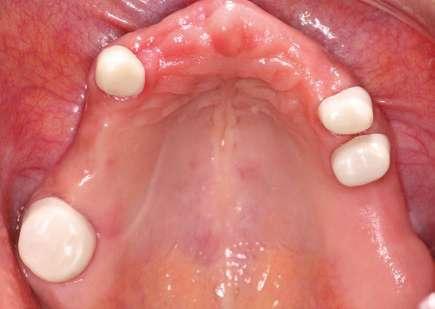

Plan de tratamiento

Basándonos en el examen clínico y radiográfico, se opta por retirar la prótesis fija superior y realizar las extracciones de los dientes fracturados, así como la eliminación de caries y cambio de amalgamas. Se realiza fase de saneamiento eliminando caries y restauraciones defectuosas, dando lugar así a un edentulismo parcial de la arcada superior (Fig. 1a, 1b). Después de efectuar el diagnóstico y anamnesis se decide no colocar implantes y hacer una prótesis removible retenida por coronas telescópicas friccionales.

Se cementan las coronas primarias siguiendo el concepto APC(8) y se coloca la prótesis a la paciente obteniendo excelente retención y pasividad. Se ajusta la oclusión y se le indican las técnicas de higiene y mantenimiento de la prótesis (Fig. 4a).

Después de un año en funcionamiento y de seguimiento, la paciente se presenta asintomática. Los

estudios radiográficos han demostrado buen mantenimiento periodontal de los dientes pilares. La paciente refiere sentirse cómoda con su prótesis, tener buena función y una estética agradable (Fig. 4b).